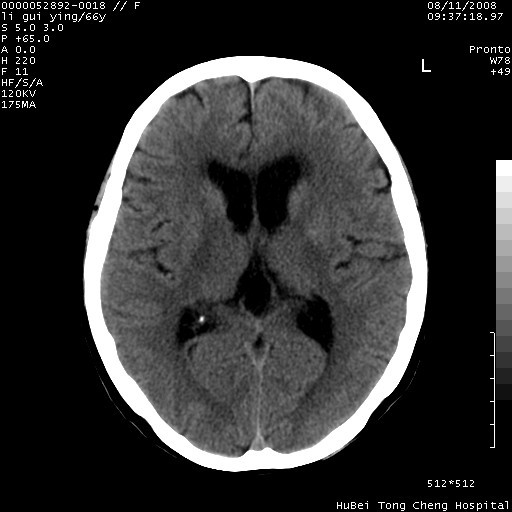

以下是引用yangyudong333在2008-8-12 12:22:00的发言:[br]1.病灶呈圆形[br]2.周围无水肿带[br]3.密度不均匀,内有点状钙化[br]4.无占位效应[br] 考虑良性占位性病变,血管瘤可能性大